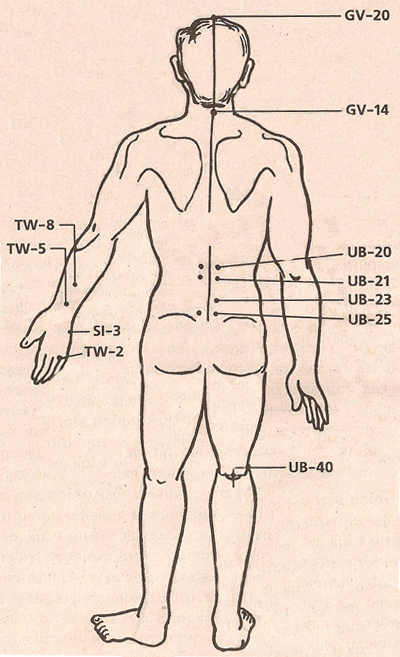

АКУПУНКТУРНЫЕ ТОЧКИ

АКУПУНКТУРНЫЕ ТОЧКИ ПРИ ЛЕЧЕНИИ МАГНИТАМИ

АРТРИТ

АКУПУНКТУРНЫЕ ТОЧКИ

Спойлер

АКУПУНКТУРНЫЕ ТОЧКИ ПРИ ЛЕЧЕНИИ МАГНИТАМИ

Спойлер

АРТРИТ

Спойлер